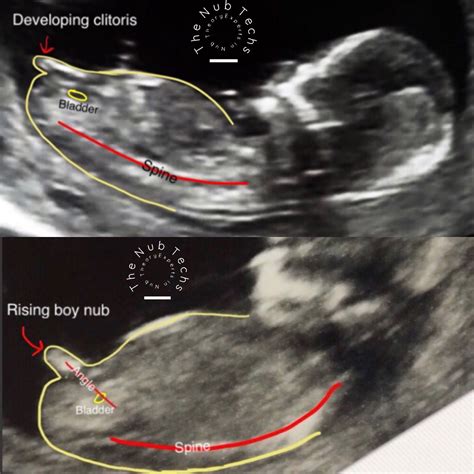

• Anatomy Check: The scan will also check for the presence of the nasal bone and other anatomical structures, which can provide additional information about the baby's health.

• 12 week ultrasound female